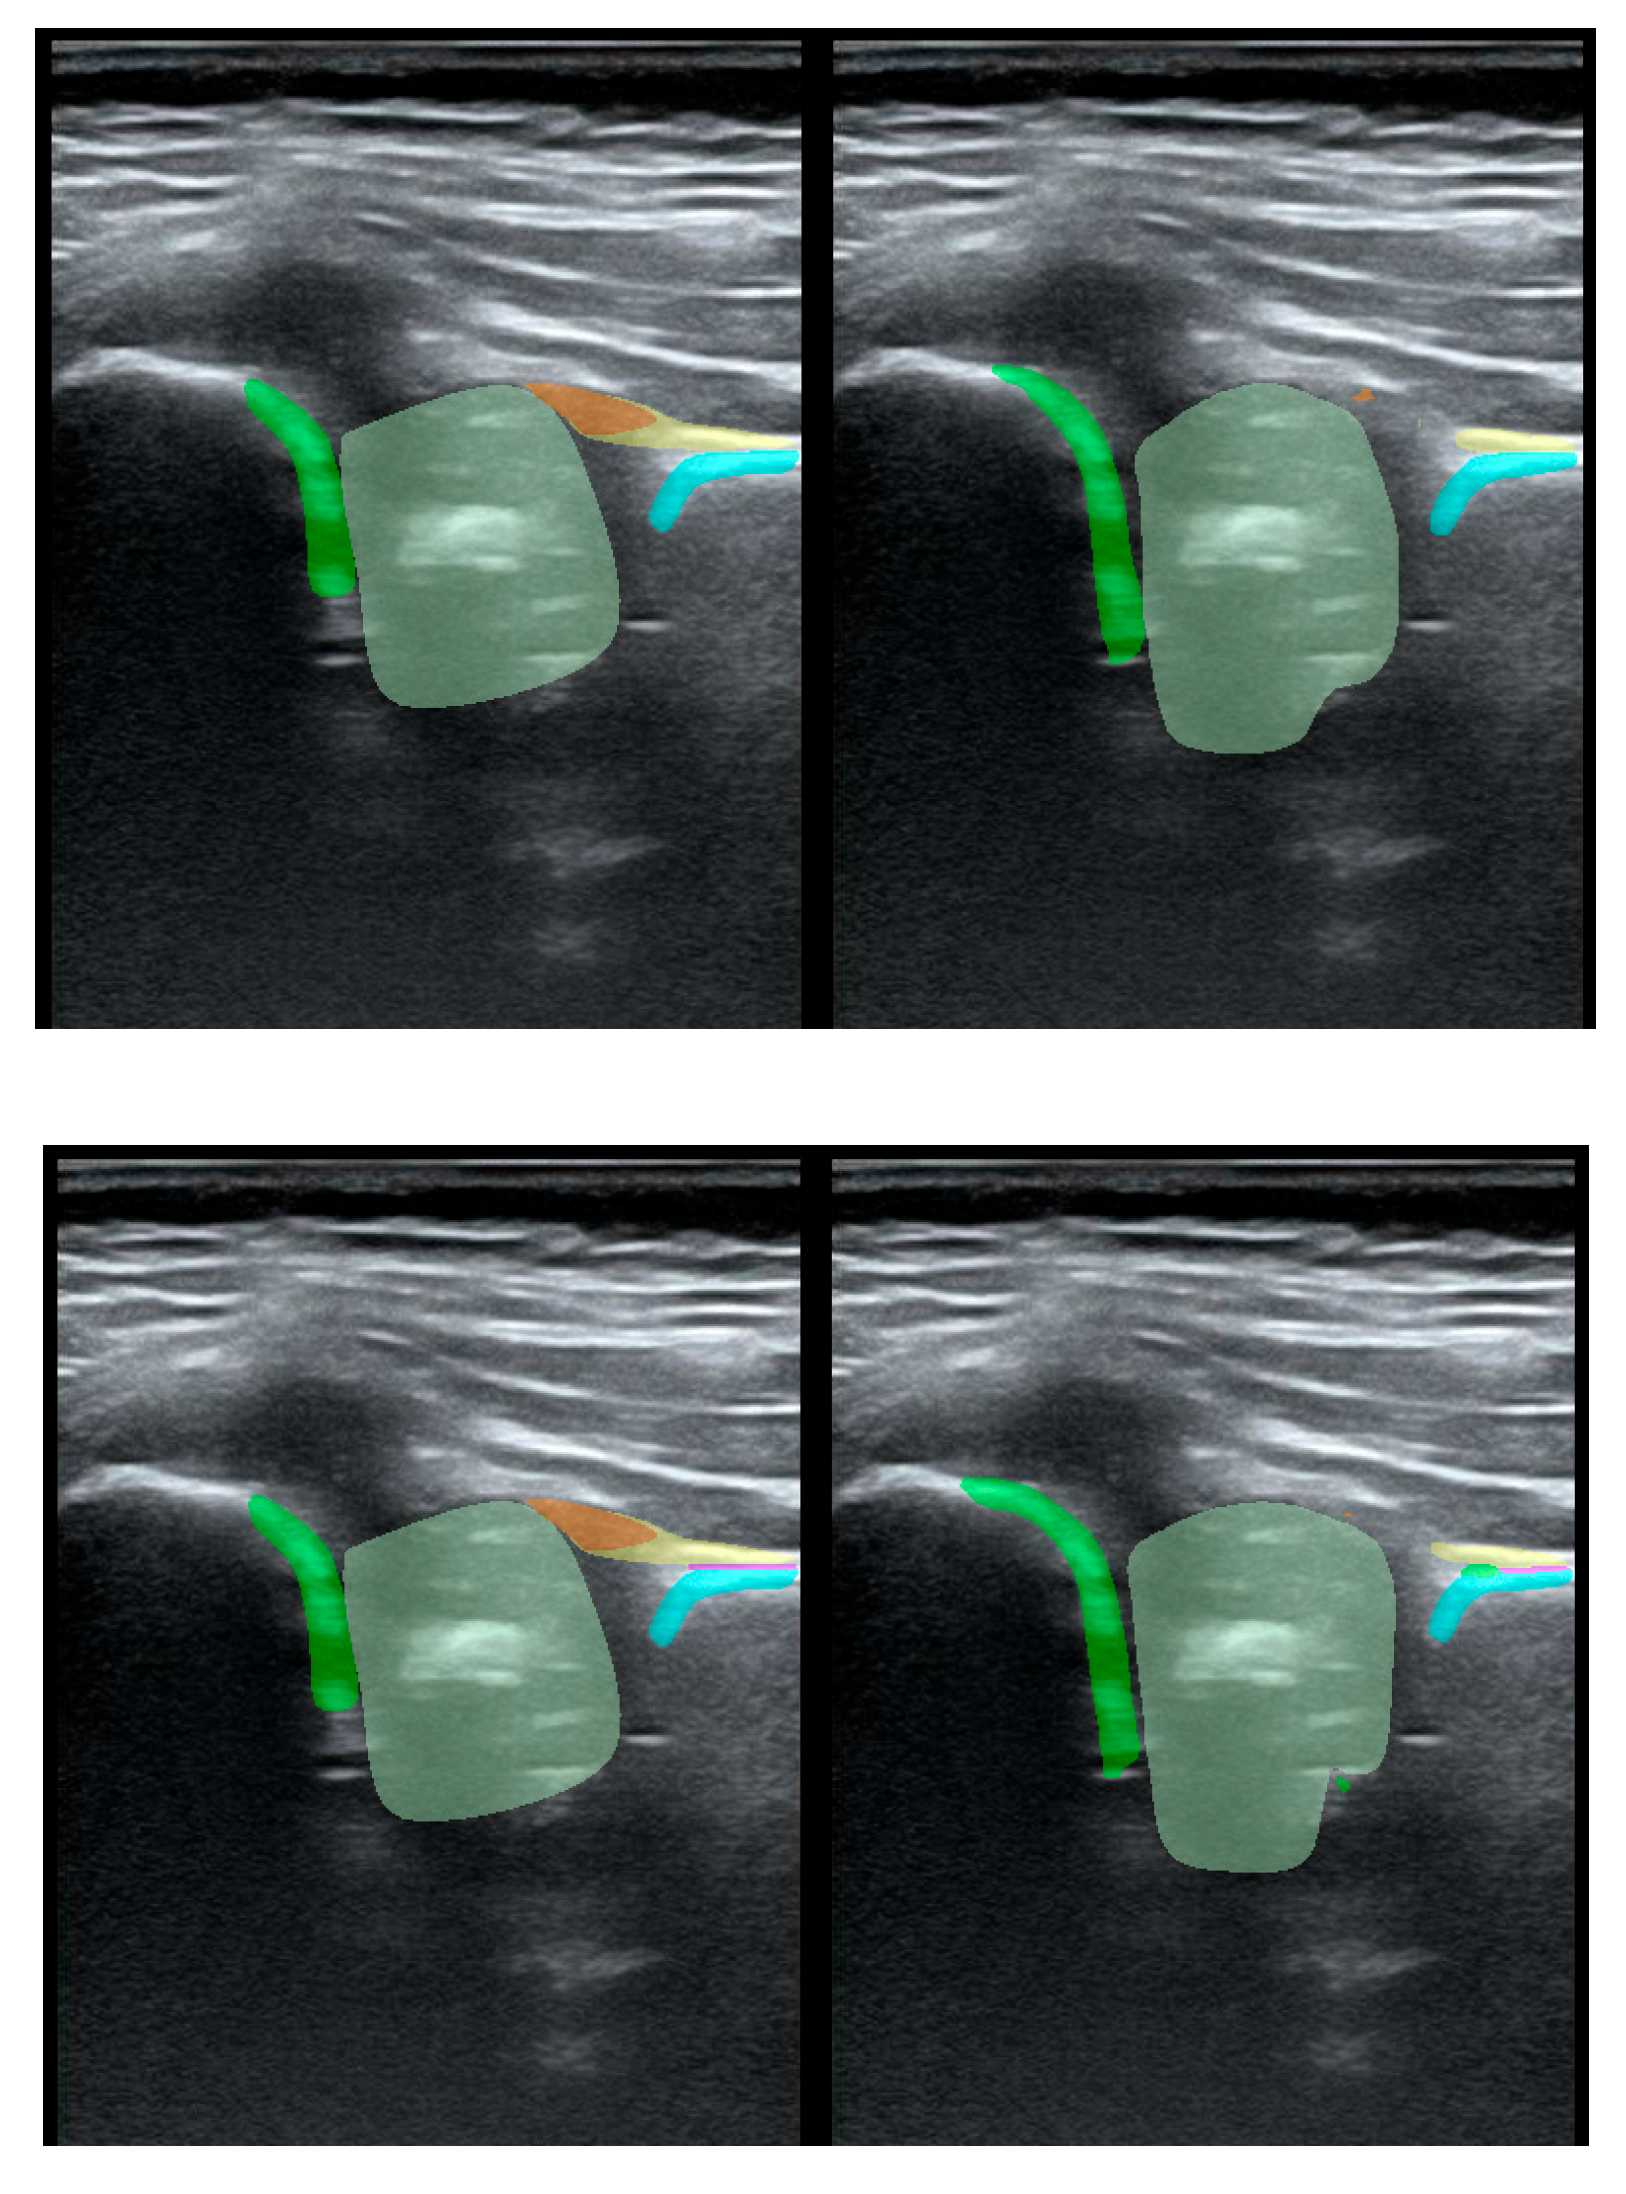

To illustrate the performance of the segmentation model, a comparison is presented between the labels obtained by the segmentation model and the ground truth labels. Two models were analyzed: Model-8 (generating segments for 8 classes) and Model-5 (generating segments for 5 classes). Both the cases with the highest quality model labels and the cases where the model labels were less accurate are presented. Figure 3 shows one of the best cases, in which Model-5 and Model-8 accurately labeled the classes relative to the doctor's labels. The worst-case scenario was also analyzed, in which the prediction results differ significantly from the ground truth labels (Figure 4).

Figure 4. Low-quality model labels (upper - Model-8) and (lower - Model-5). Annotated mask on the left, model mask on the right.